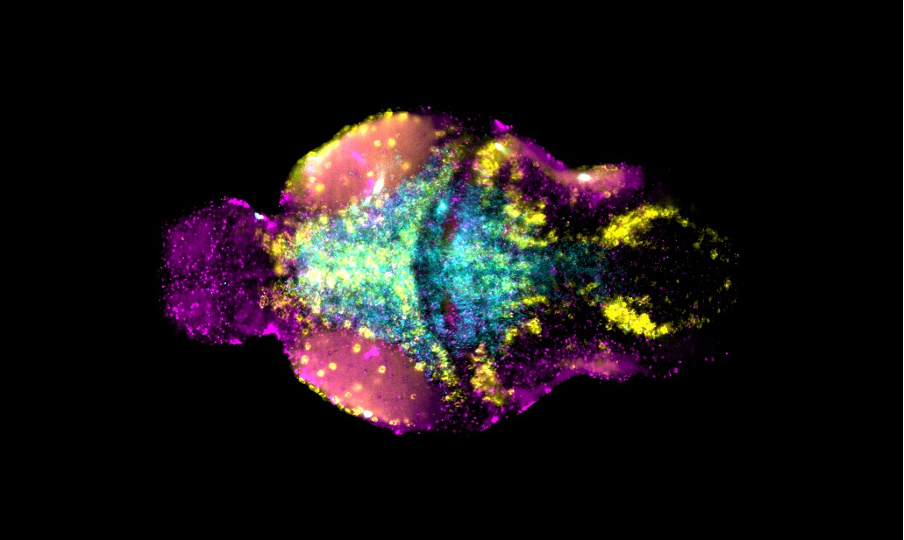

MRI brain

Our lab uses manganese transporter mutant zebrafish as models for manganese overload/deficiency in order to dissect how metal dyshomeostasis disrupts neurons, synapses and circuit function with the view to identifying new therapeutic targets. In addition, we are working to develop novel therapeutic approaches to improve treatments for disorders associated with Mn neurotoxicity.